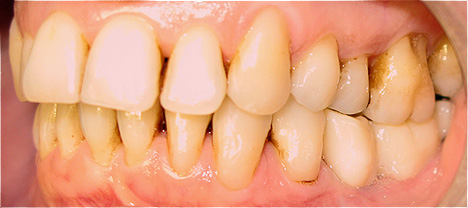

Caso 1 - Implante imediato após extração do dente fraturado (dente 11) e implante imediato

![]() |